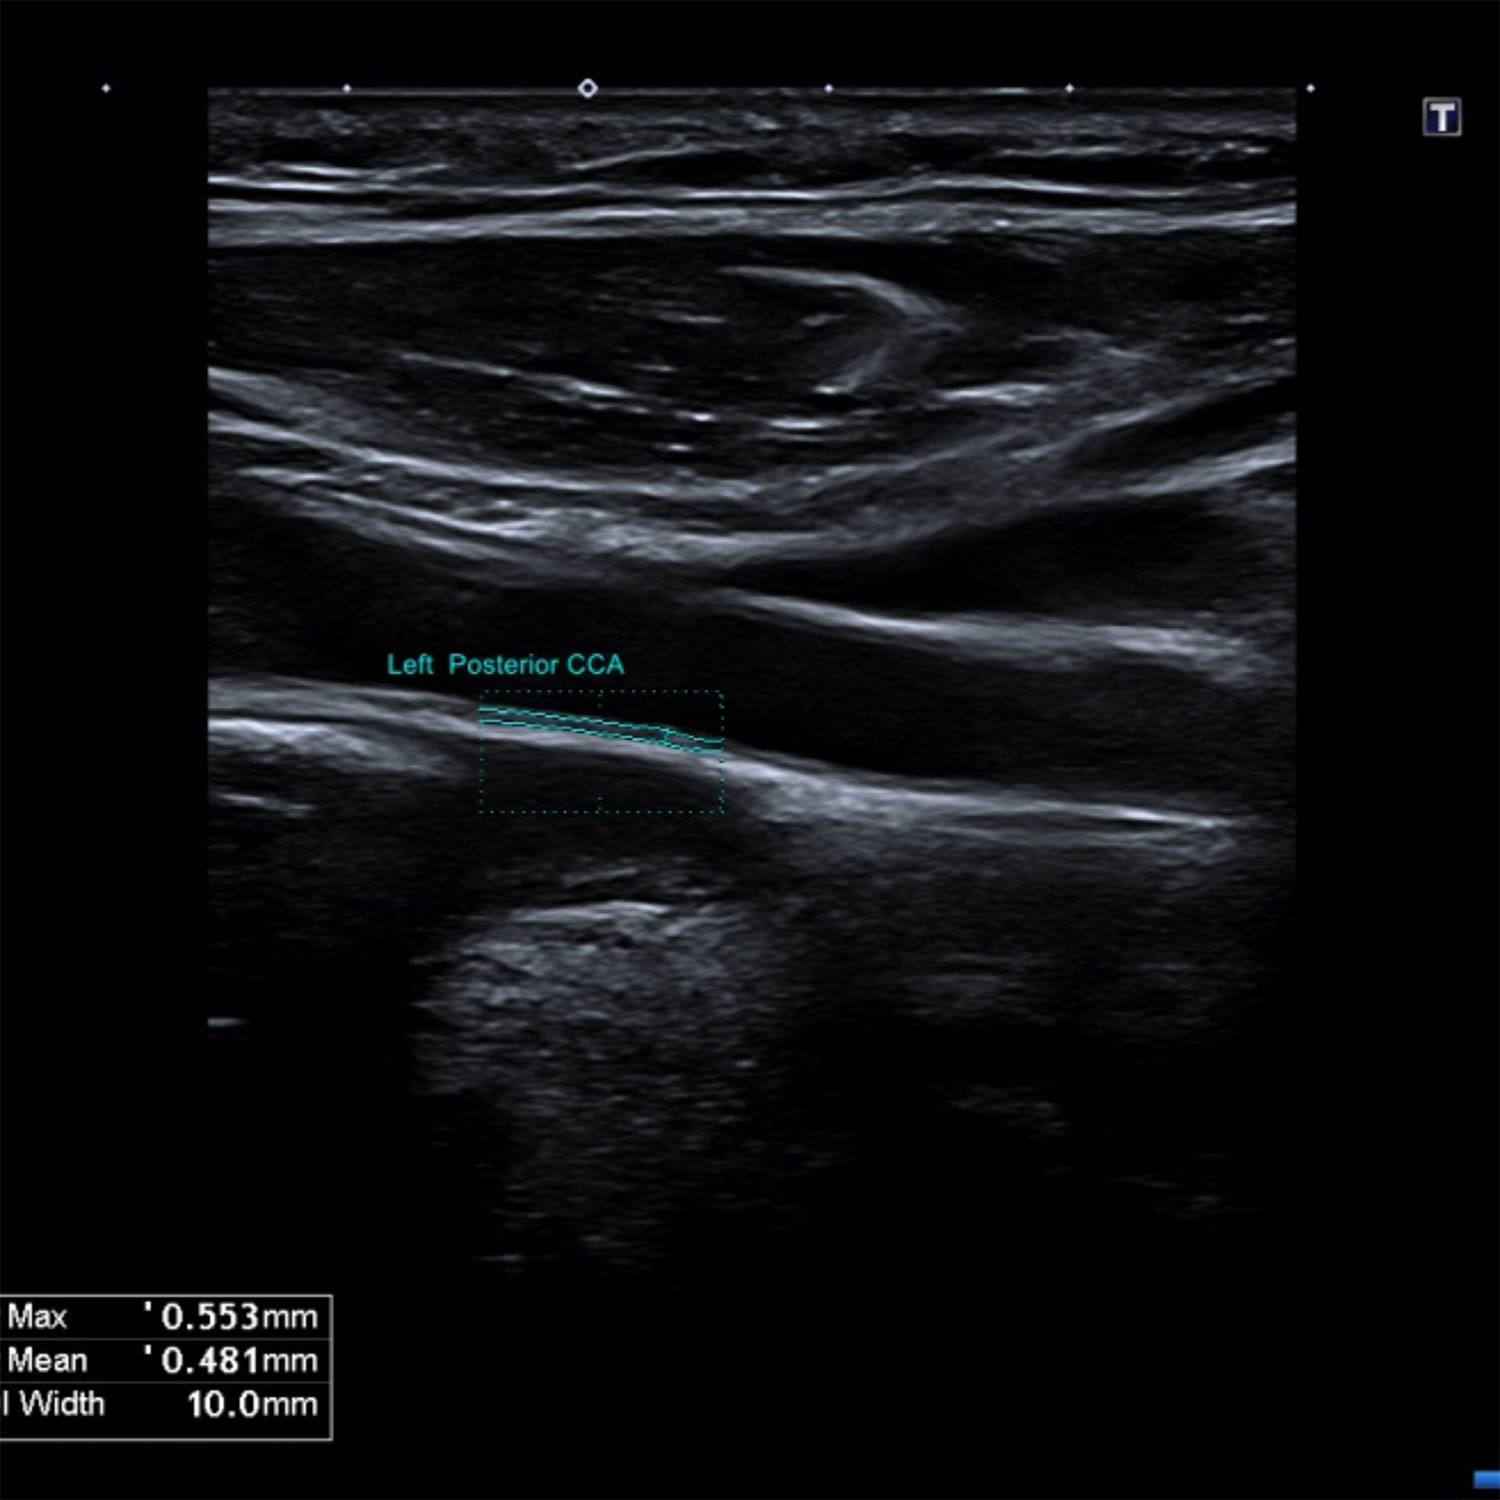

Doppler veineux et artériel images d'examen